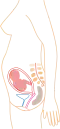

Stadia in beeld

- (aantal maanden refereert aan PML)

1 maand

1 maand 2 maanden